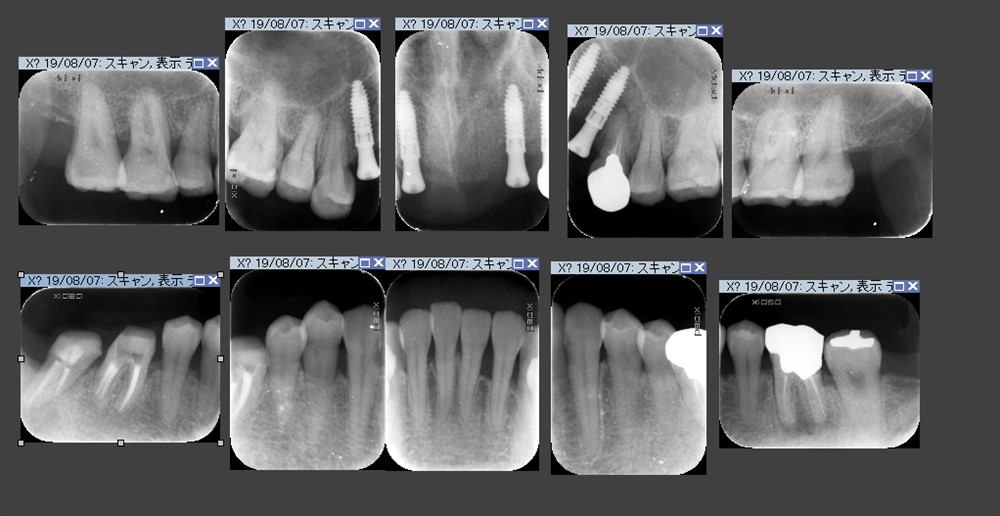

この時点で無切開のインプラントを上の前歯に入れました。

その時のレントゲンです。

不思議です。見る人が見ると分かると思いますが右上、右下で骨の再生が見られます。

この治療も歯周病の再生手術をしておりません。

再生材料も全く使用しないレーザーのみの基本治療のみです。

血餅が安定するように治療しています。

日付をみて頂くとお分かりになるかと思いますが歯周基本治療に約1年掛かっています。

これが大切!細菌のコントロールをしてからインプラントです。